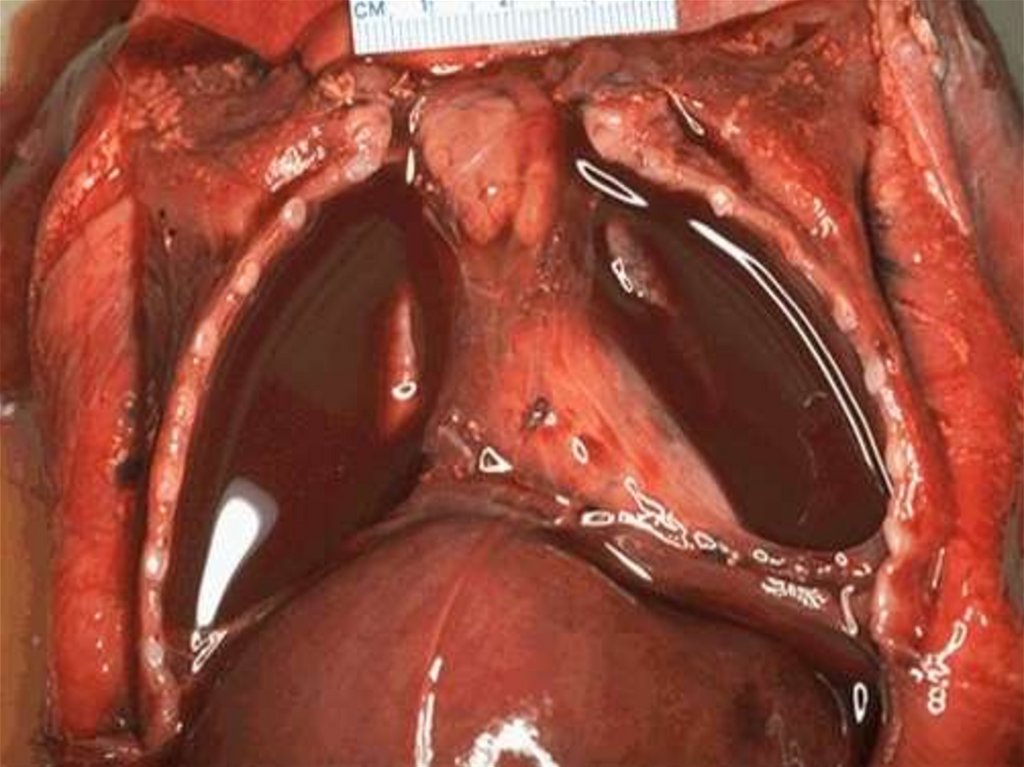

Тромбоз нижней полой и левой общей повздошных вен.

22. Тромбоз нижней полой и левой общей повздошных вен.